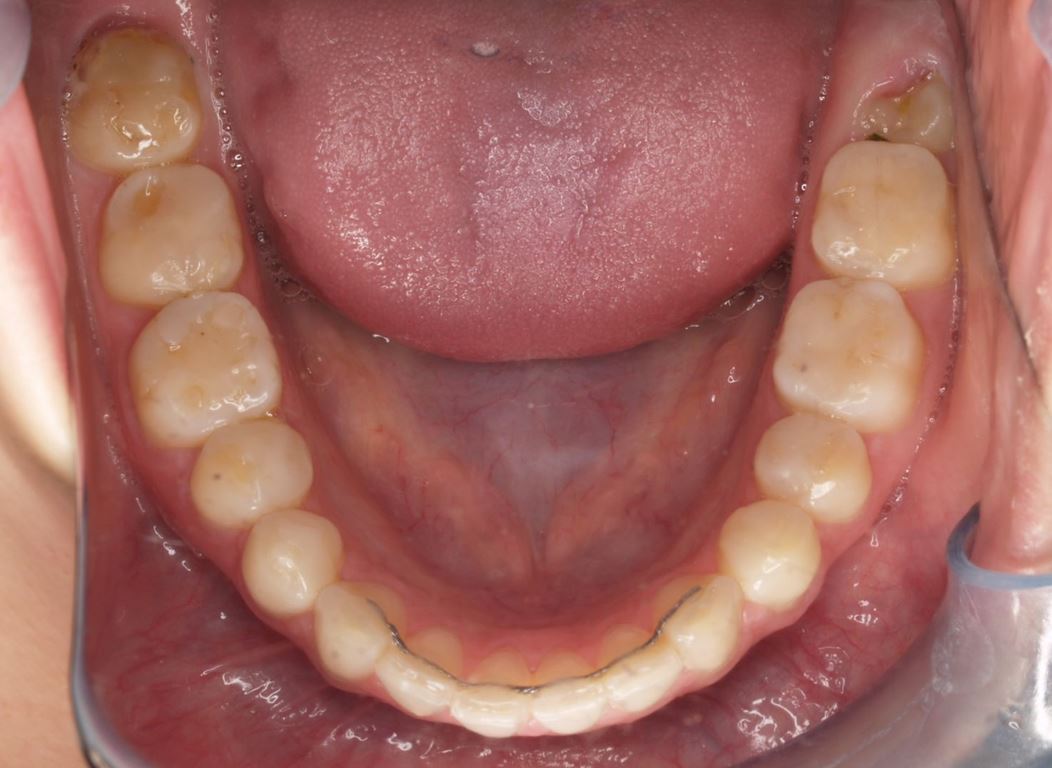

W pierwszym etapie diagnostycznym wykonano zdjęcia zewnątrz- i wewnątrzustne (ryc. 1-12).

Ryciny 39-50 przedstawiają stan po zakończeniu leczenia.